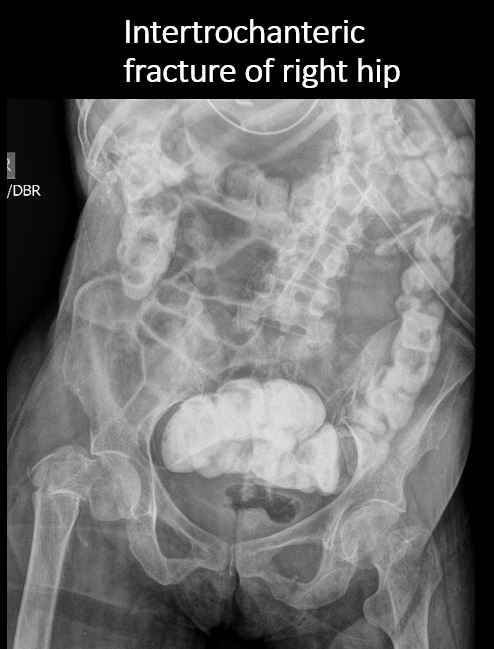

There is an acute or chronic fracture of the spine, pelvis, femurs, or ribs. [Yes/No]